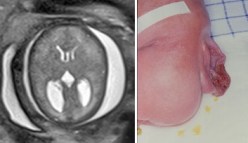

il peut être fait en anténatal ; c’est souvent devant une hydrocéphalie qu’un spina bifida initialement passé inaperçu est finalement découvert. c’est un élément de mauvais pronostic dévelopmemental.

le diagnostic est souvent fait à la naissance, après fermeture de la myéloméningocèle, devant une tension de fontanelle, augmentation du PC, parfois des fuites de LCS au niveau de la cicatrice lombaire.